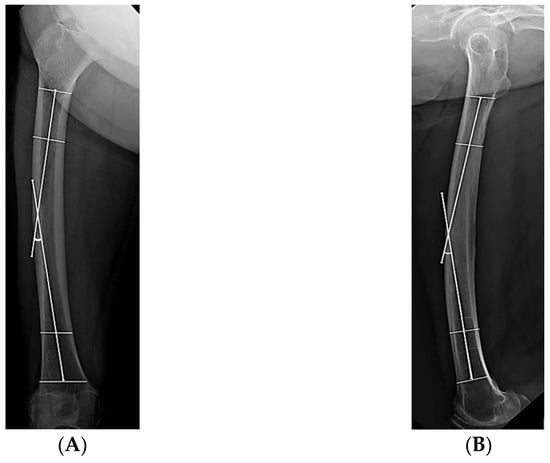

| Lateral bowing, ° | 14.7 ± 5.9 (2.4–24.8) | 7.9 ± 6.5 (0.2–21.9) | <0.001 b |

| Anterior bowing, ° | 16.6 ± 4.2 (9.7–25.1) | 13.0 ± 7.8 (1.0–29.5) | 0.008 b |

| Lateral bowing, ° | 1.154 (1.065–1.251) | <0.001 b | 1.205 (1.046–1.389) | 0.010 b |

| Anterior bowing, ° | 1.067 (0.997–1.141) | 0.061 | 1.048 (0.915–1.199) | 0.500 |